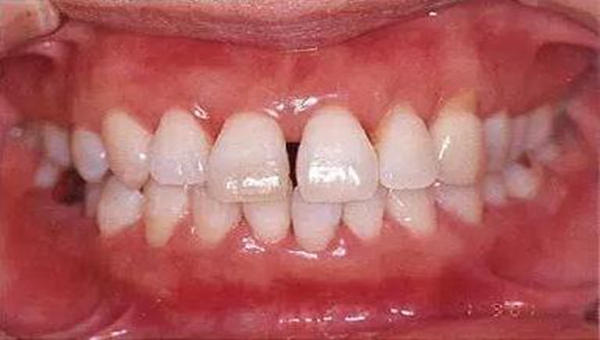

●健康且正常的牙周組織臨床圖像